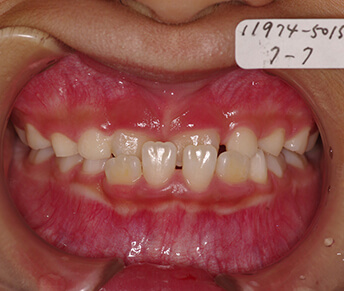

子供の矯正(乳歯がある時期)

|

- | 3~6ヶ月 | 100,000円 |